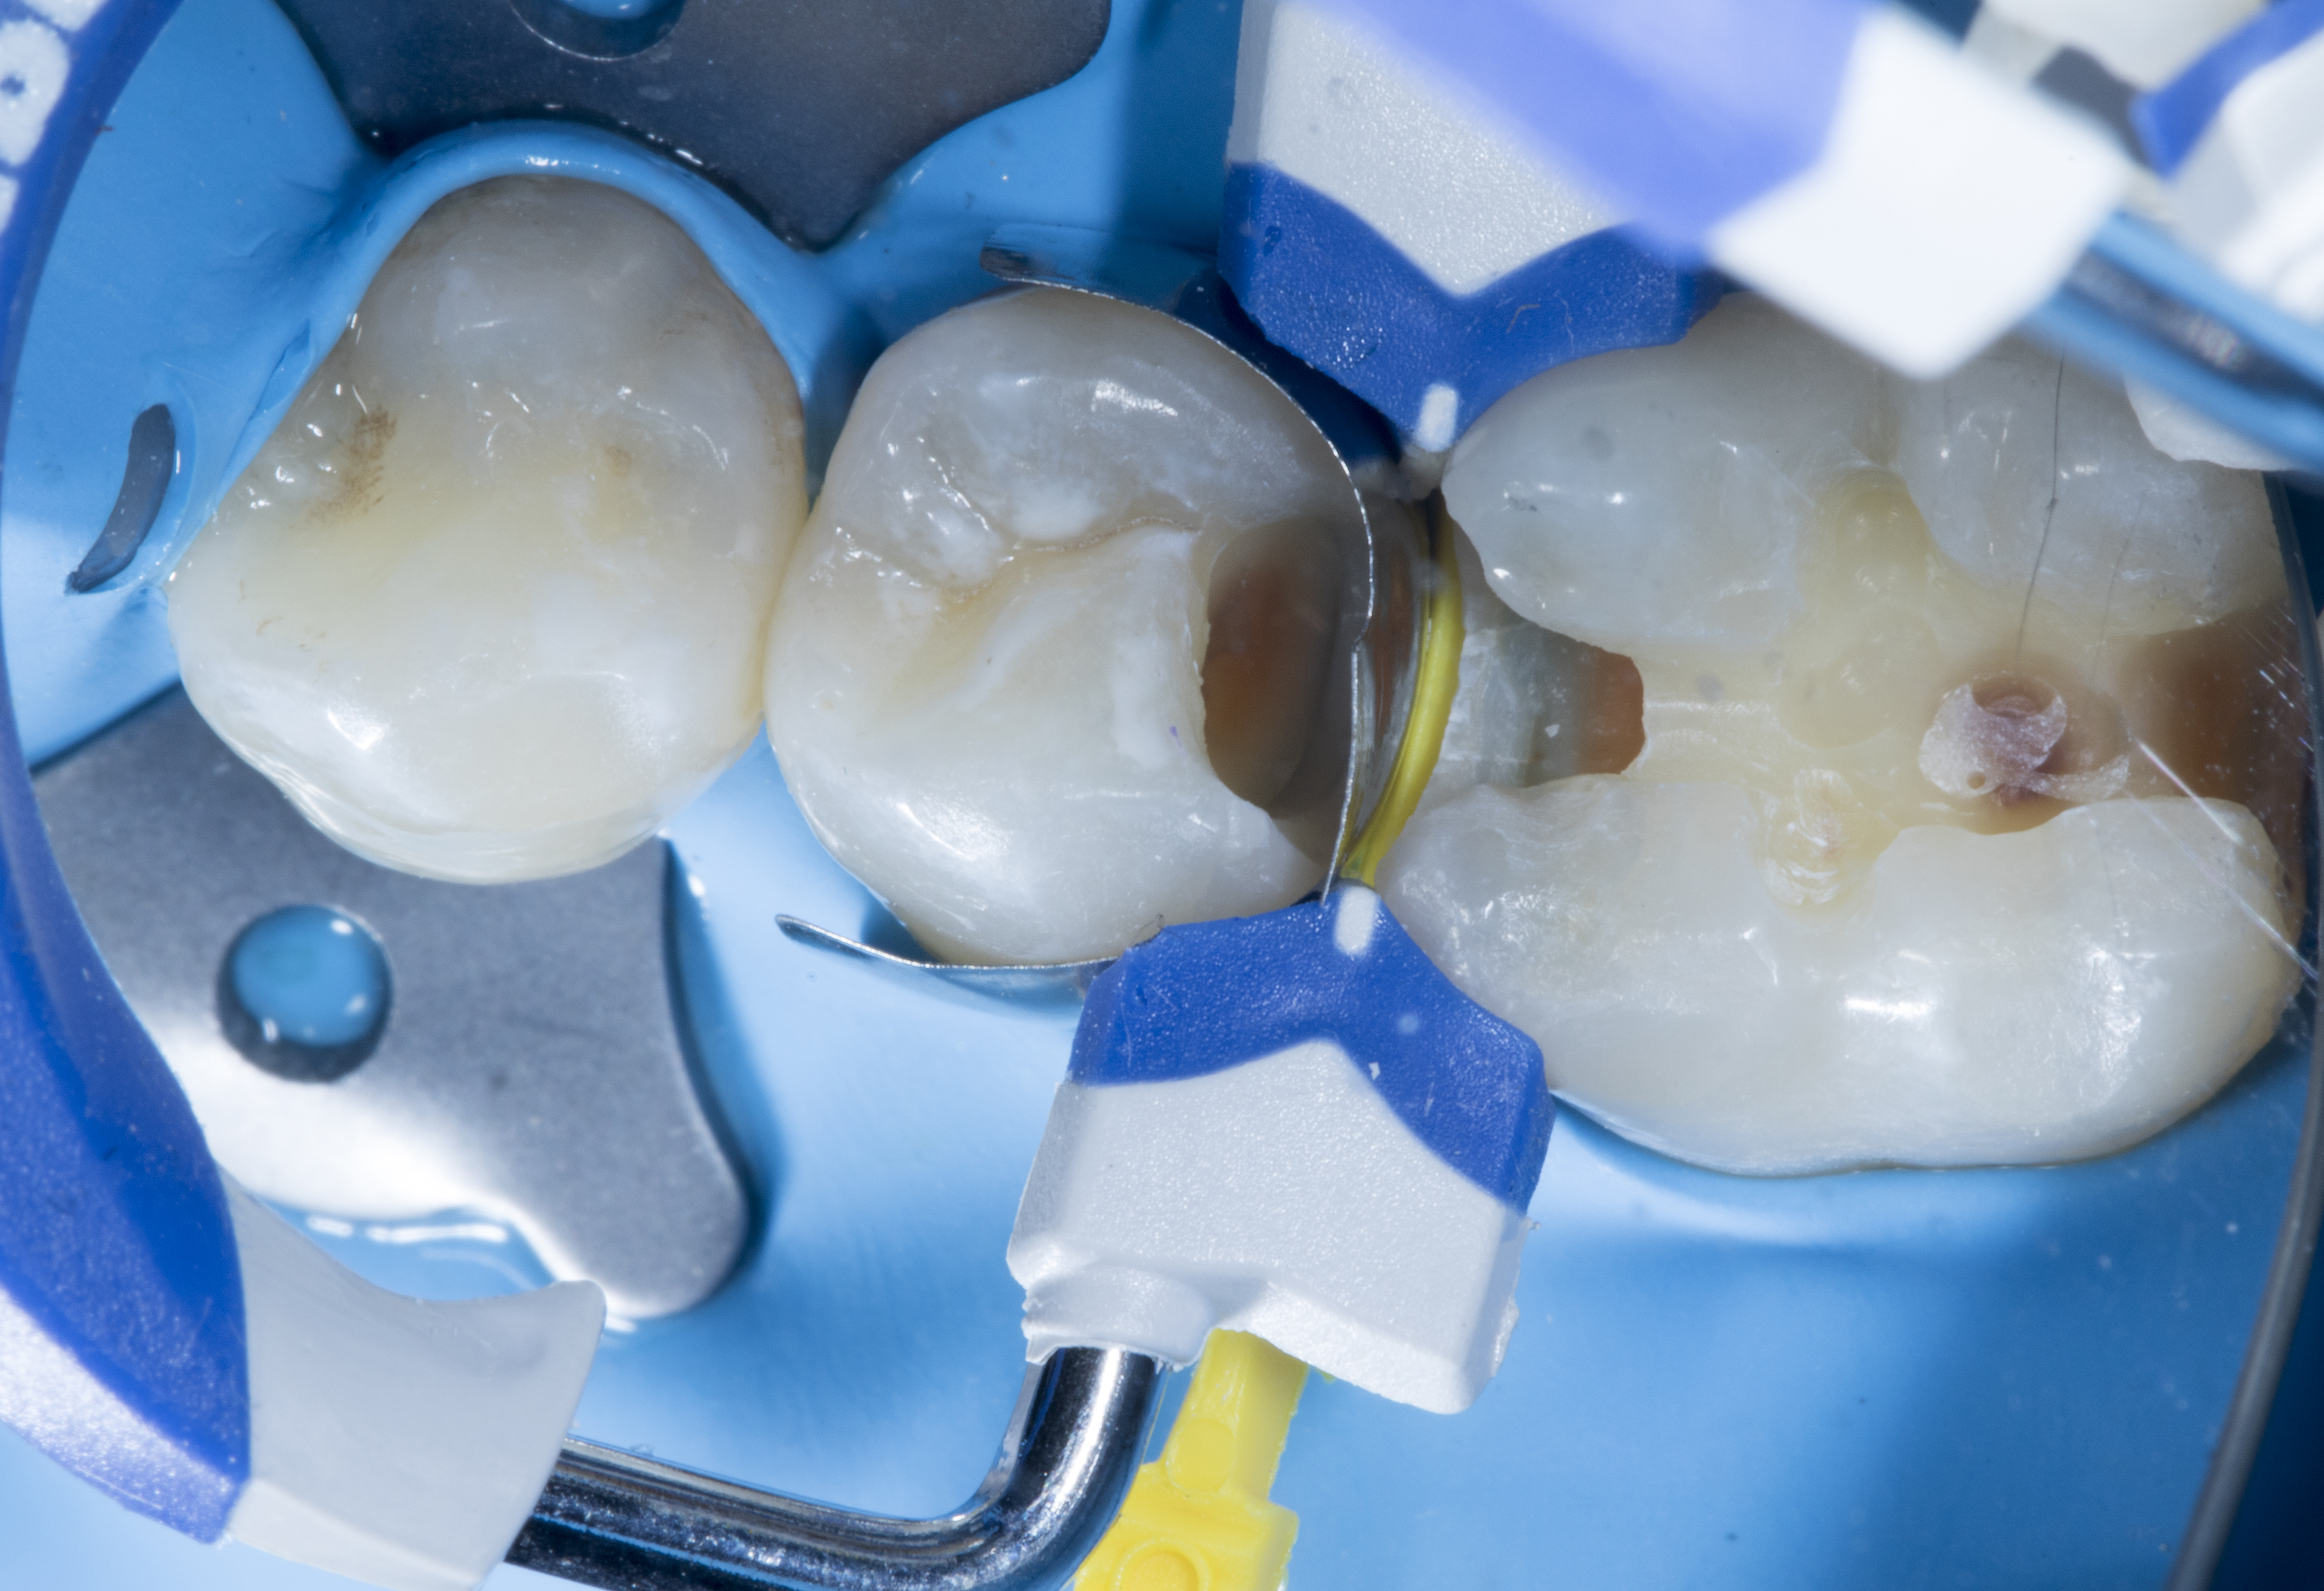

Step 2 – Restoration of tooth #35. After the initial cavity preparation, a deeper carious lesion was identified. Caries dye was applied to effectively remove caries with the help of a slow speed round carbide bur.

Figure 2

Figure 2. After the initial cavity preparation a deeper carious lesion was identified.

Step 4 – In order to achieve a natural contact, tooth #35 was restored first followed by tooth #36.

A Garrison pre-contoured premolar FX100 (gray) matrix band was placed in between #35 and #36. Then an extra small (yellow) Fusion Wedge was placed in between. This provides a wedging effect and sealing of the band with the proximal box so that when composite is placed in the box it won't flow excessively beyond the band.  This is the most common failure seen in Class II’s.  Additionally, the wedge stabilizes the band during ring placement (Composi-Tight 3D Fusion FX400 blue, short ring), preventing the band from moving.  This is the most important step in doing perfect Class II restorations.

Figure 4

Figure 4. A Garrison pre-contour premolar FX100 (grey) band was placed in between #35 and #36 along with an extra small (yellow) Fusion Wedge.